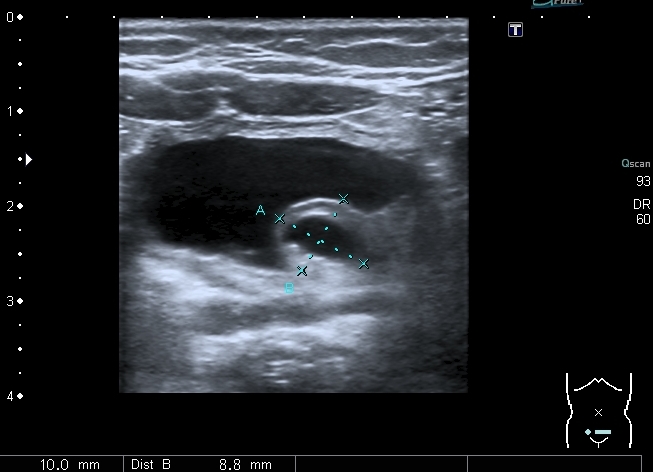

Ребёнок 3 месяцев , госпитализирован в связи с изменениями в анализах мочи (лейкоцитурия, протеинурия).

При УЗИ: правая почка - не изменена, в левой - незначительное расширение ЧЛС

В нижней чашечке левой почки - конкремент до 5 мм

Конкремент даёт твитлинг - артефакт

В мочевом пузыре определяется достаточно большое уретероцеле слева, периодически увеличивающееся и пульсационное уретероцеле справа. Левый мочеточник в нижней трети резко расширен.